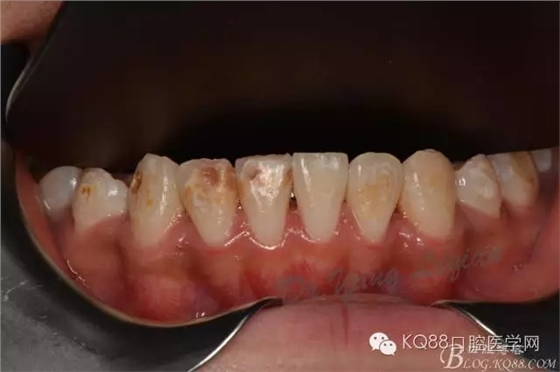

小美女今年16歲,正畸結(jié)束后下前牙唇側(cè)齲壞嚴重,影響美觀??紤]到患者年齡較小,所以和家長商量后決定現(xiàn)行樹脂貼面暫時修復,待成年后重新制定修復計劃。

圖片由助理拍攝,比較雜。31只是做了拋光沒有做貼面。齲壞脫礦位置質(zhì)地較軟,小球鉆仔細去除,硅膠車針拋光。